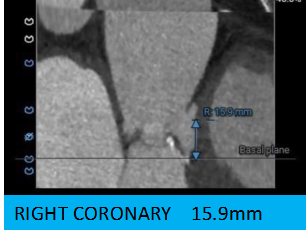

3.左冠开口高度偏低,瓣叶较长,冠脉风险较高,右冠高度可。

2.术前CT影响评估显示:左冠开口高度为11.0mm,左冠瓣瓣叶长度为17.7mm,存在冠脉阻挡风险。

主动脉根部评估:

冠脉评估: